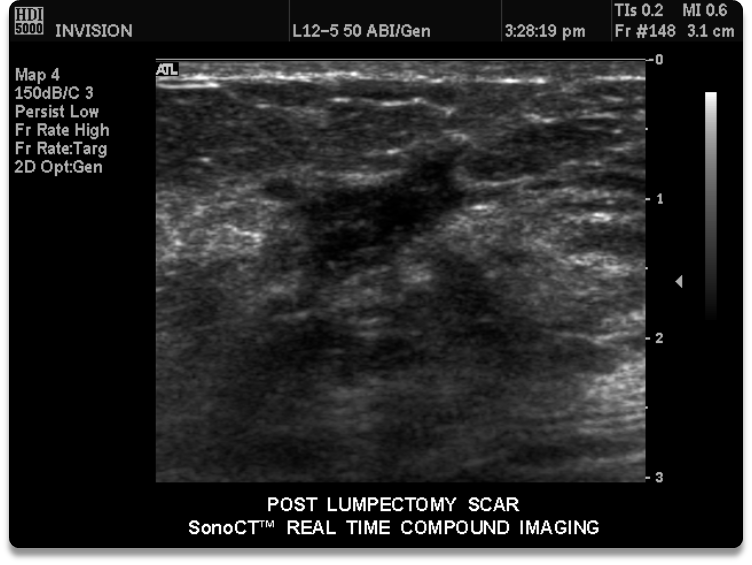

What is this image showing

a lumpectomy scar